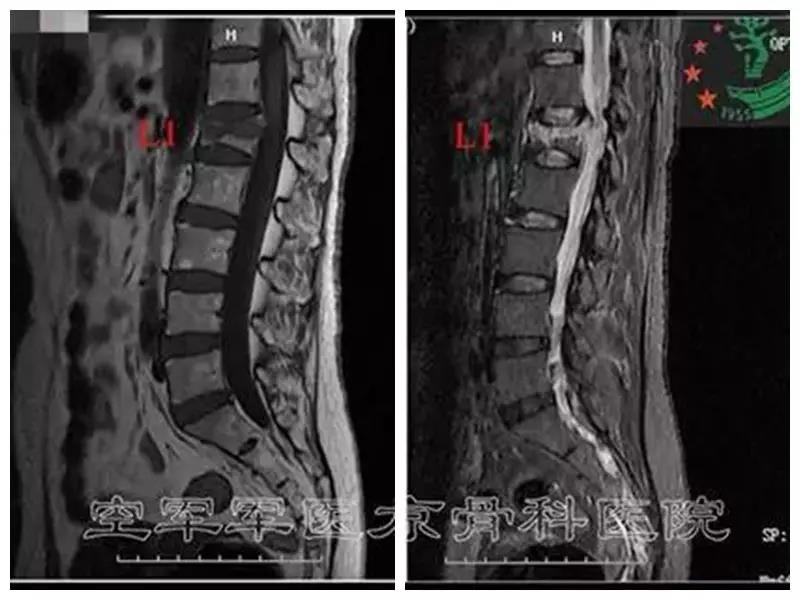

术前MRI

术后X线片正侧位及三维CT